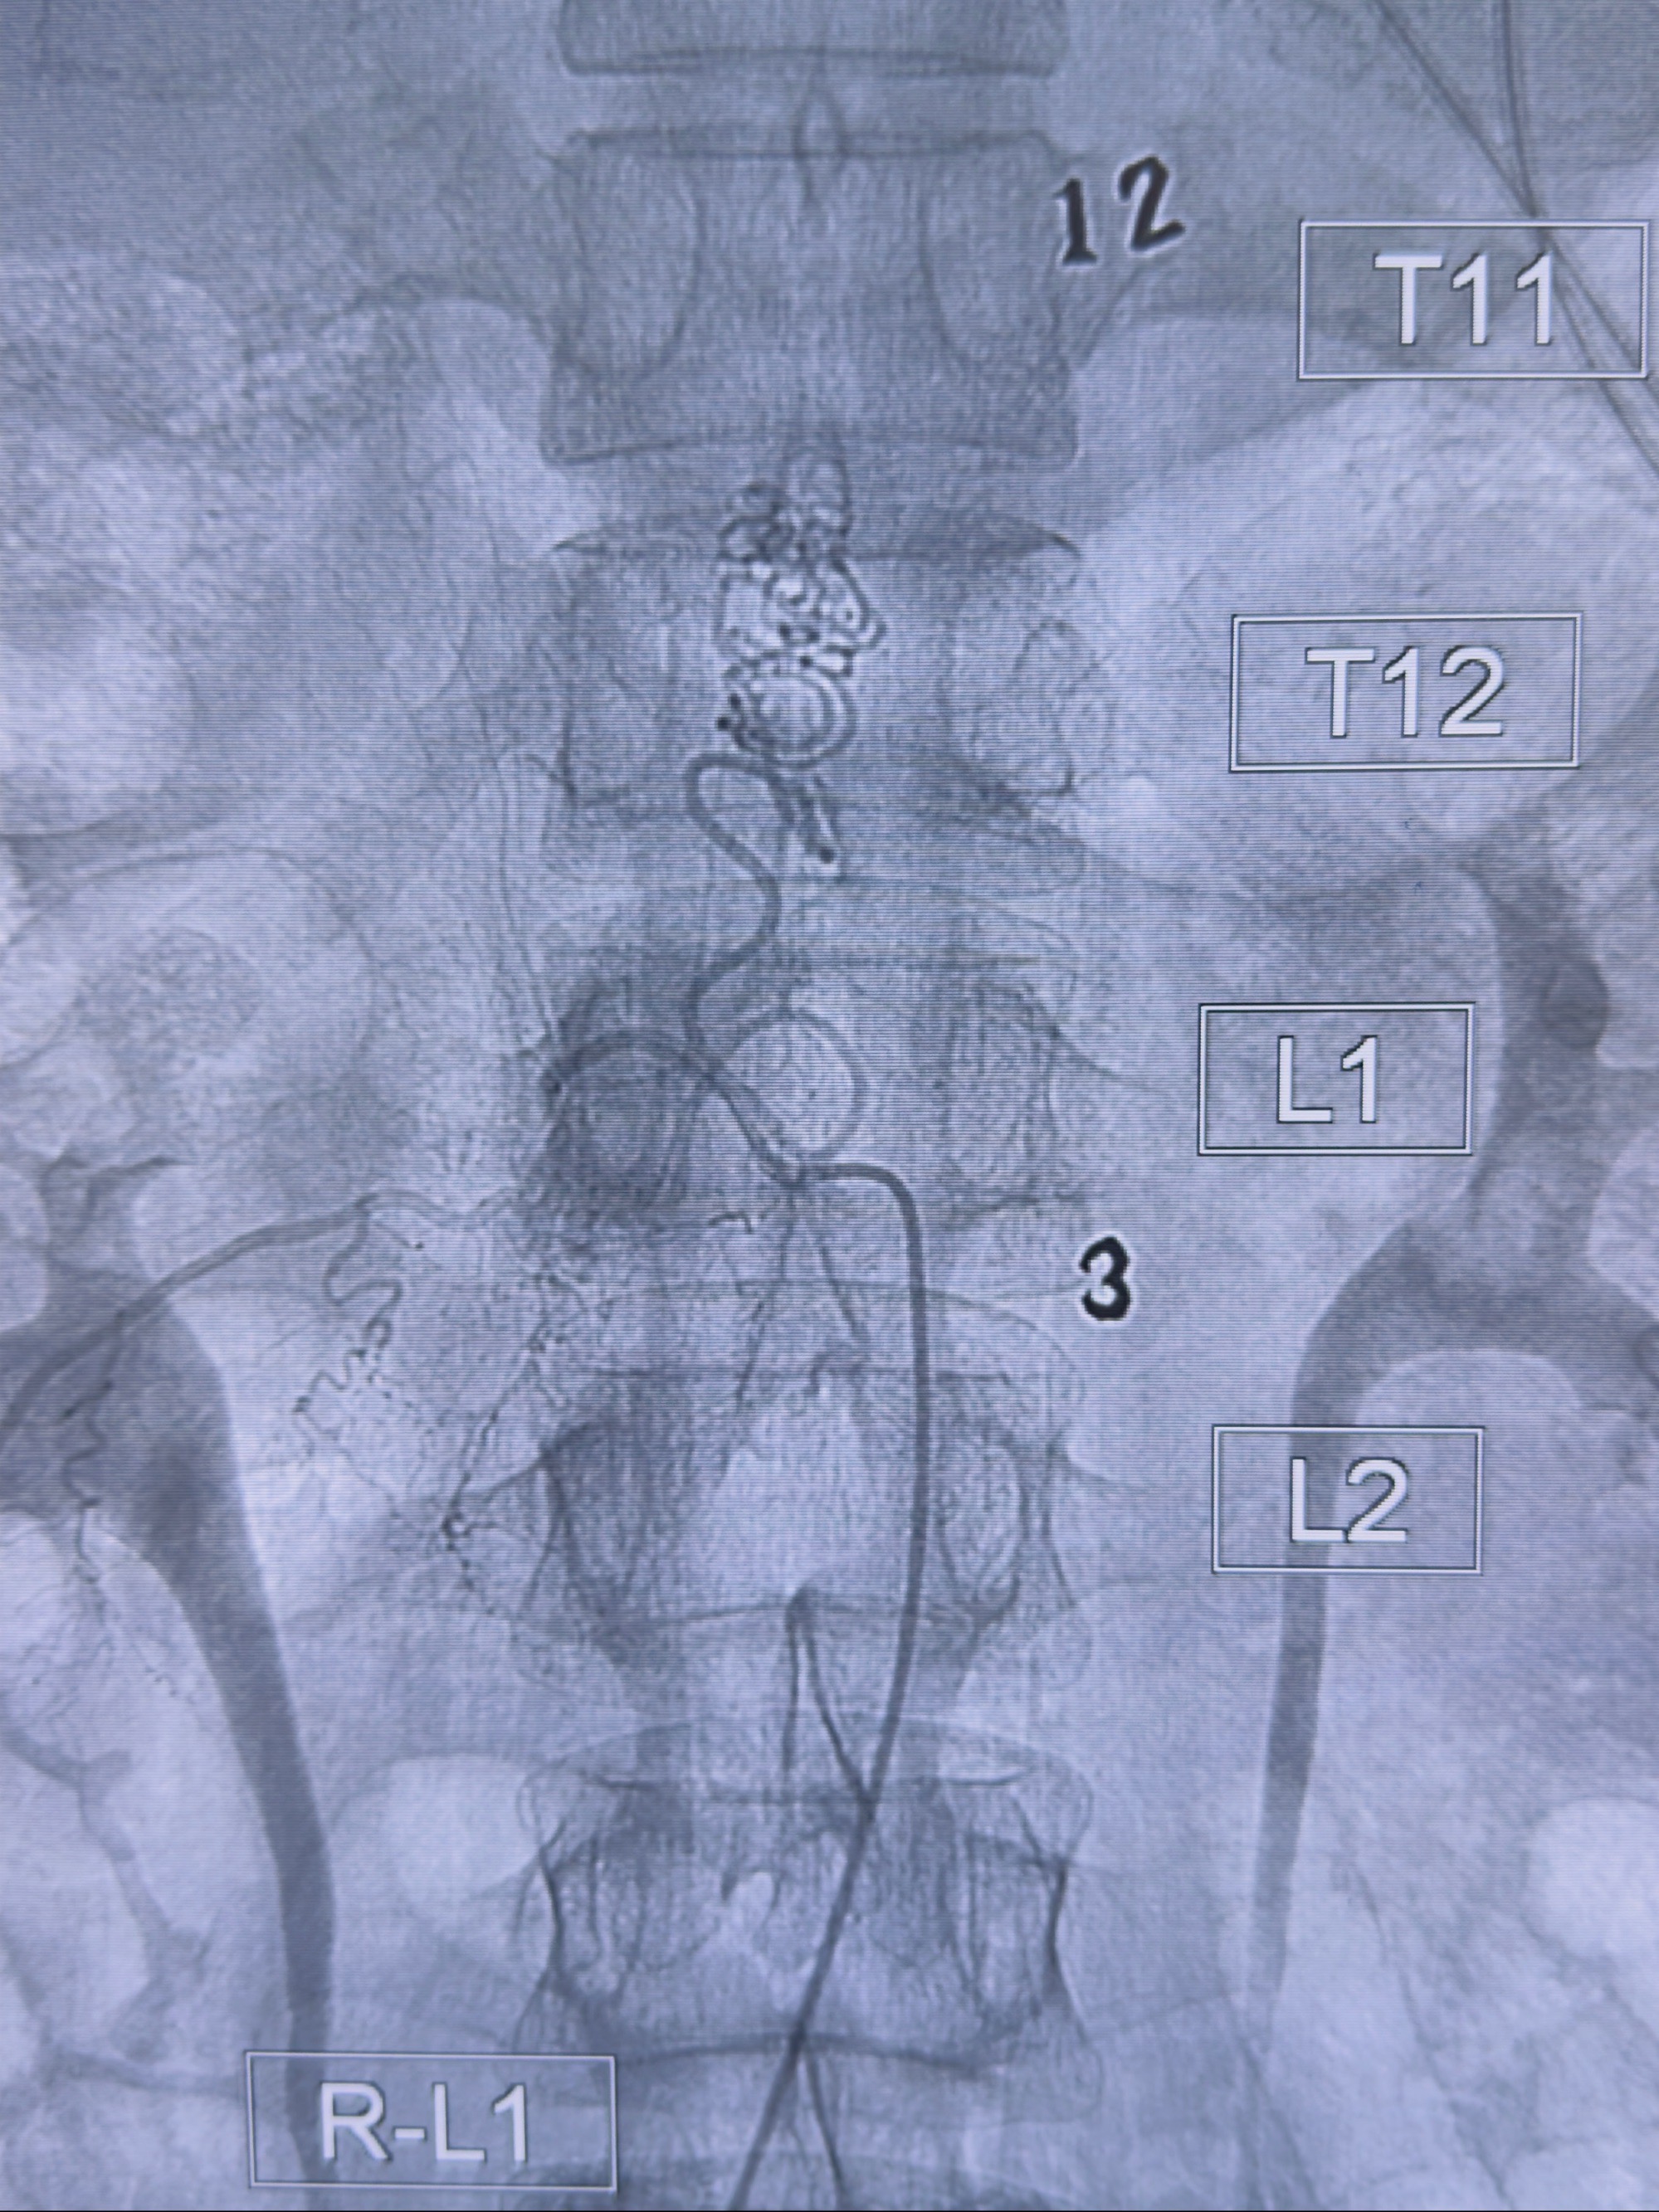

2023-10-13DSA:右侧L1水平硬脊膜动静脉瘘,供血动脉为右侧L1,附近动脉未见明确吻合供血,供血动脉处可见脊髓前动脉发出

1.建议外科手术,已行美兰定位c